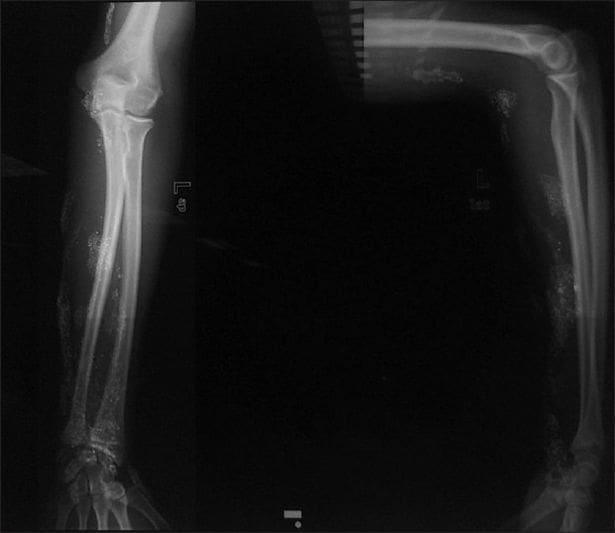

Y es que, en su afán de ser superhéroe de Marvel, este adolescente sacó mercurio de un termómetro casero y con una jeringa, se lo inyectó en el brazo vía subcutánea.

Como era de esperarse, la piel del joven reaccionó al estar en contacto con la sustancia tóxica para el cuerpo humano. Esto le ocasionó una úlcera que no cicatrizó.

“Se realizó un procedimiento quirúrgico para tratar la úlcera y reducir los niveles de mercurio en sangre y orina,” se explicó en el informe.

“Sin embargo, el paciente no desarrolló signos clínicos de intoxicación crónica, lo que demuestra que la inyección subcutánea de mercurio tiene un riesgo bajo de toxicidad sistémica”, se explicó en el informe.